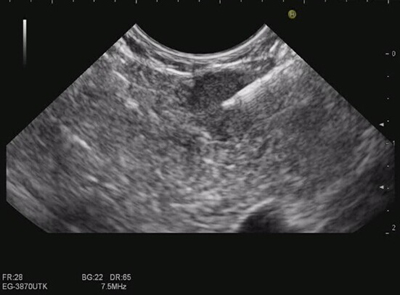

患者陈××,女,62岁。以上腹不适10余天之主诉入院。10余天前因上腹不适,就诊于当地医院。行胃镜检查示十二指肠溃疡,胃壁内隆起性占位,胃体粘膜下良性肿瘤?遂转至我院消化科行超声胃镜检查,针对胃壁病变进行超声提示为胃体小弯侧固有肌层低回声占位,考虑胃体间质瘤。当完成目标病变的扫查后,以超声内镜常规进行胆胰系统的扫查,在患者胰腺颈部发现一处低回声占位,血流多普勒显示病变血供丰富,最大截面大小为9mmx6mm,弹性成像显示病变较软,彻底扫查胰腺其余部位后未再发现异常回声。行胰腺薄层CT未能发现病变。征求患者同意于超声内镜引导下,经胃壁进行细针穿刺,为减轻患者痛苦,行笑气吸入麻醉,马师洋主治医师以22G穿刺针反复于胰腺颈部微小病变内抽吸组织及细胞,得到了充分的组织标本,患者全程配合良好,术后在胃镜下可见局部胃壁微小针眼,无需特殊治疗即可当日进食。术后病理片经多家医院会诊后,确诊为:低分化小细胞神经内分泌癌。患者将随之接受微创手术治疗,有望根治这一恶性肿瘤。